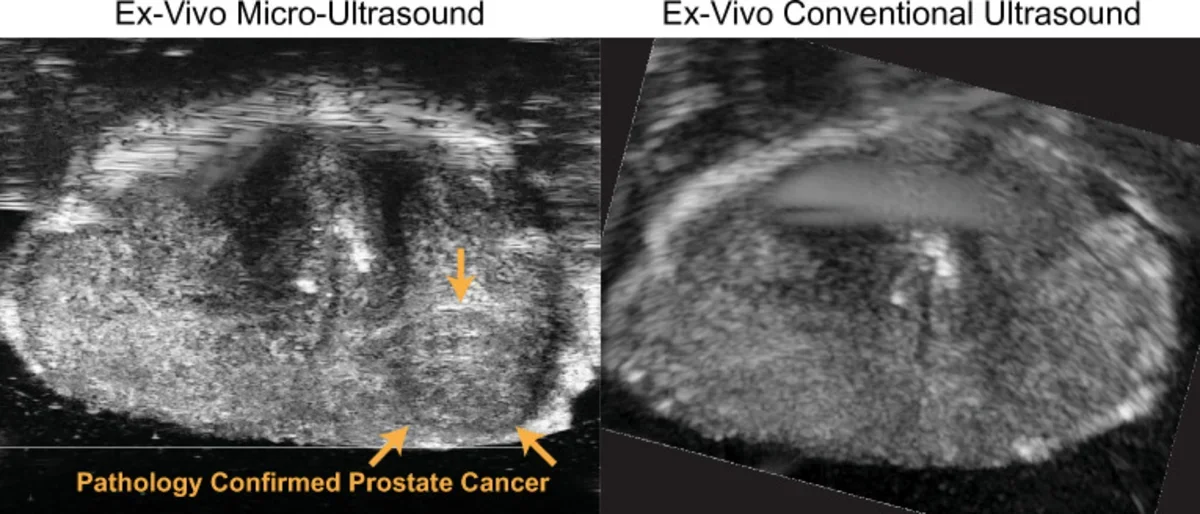

Ultrasounds of Pathology Confirmed Prostate Cancer

Evaluation of Prostate Cancer Detection Using Micro-Ultrasound Versus MRI through Co-Registration to Whole-Mount Pathology

Micro-ultrasound has recently been introduced as a low-cost alternative to multi-parametric MRI for imaging prostate cancer. Early clinical studies have demonstrated promising results; however, robust validation via comparison with whole-mount pathology has yet to be achieved. Due to micro-ultrasound probe design and tissue deformation during scanning, it is difficult to accurately correlate micro-ultrasound imaging planes with ground truth whole-mount pathology slides. In this study, we developed a multi-step methodology to co-register micro-ultrasound and MRI to whole-mount pathology.